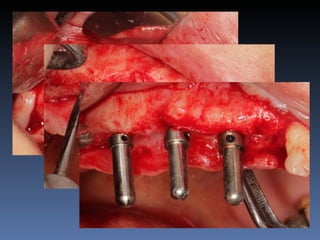

BOX 2

Sebastião Moreira Souza

Idade – 49 anos

Sexo – Masculino

Raça – Caucasiana

ASA – II

Data- 23-04-2012

Diagnóstico: Desdentado total maxila

Plano de tratamento:          Reabilitação com 6 blocos

“onlay” e “sinus-llift” bilateral, provenientes de Úmero

fresco-congelado (FFB); reabertura para instalação

de 6 implantes dentários endo-ósseos e reabilitação

protética fixa.

21-09-2011

23-04-2012

Zona 2.3

3,5 mm

Pré reabilitação

Reabilitação Aloenxerto

Instalação Implantes